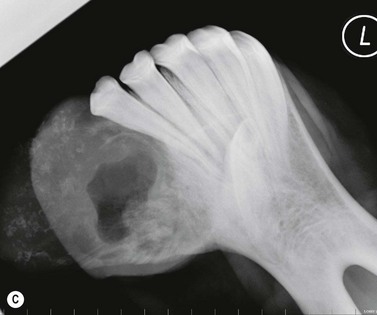

The condition is usually presented as a painful, hot, progressive swelling of the mandible with a characteristic ‘sun-burst’ radiographic appearance of bone lysis and irregular deposition of trabecular reactive new bone44 (Fig. 11.12). Pathological fractures can occur in affected bones.

image image image image image

Fig. 11.12 (A) & (B) This 5-year-old Irish Draught mare was presented with a 4-week history of a mandibular swelling, gingival bleeding, weight loss and dysmasesis. The mandibular incisors were palpably loose and the mandible was warm to the touch and mildly painful on palpation. (C) & (D) Lateral and occlusive radiographs gave the suspicion of a neoplastic lesion. (E) A bone biopsy was taken from several sites, and the horse was diagnosed with osteosarcoma.

Diagnostic confirmation

Their radiographic appearance is highly suggestive, but biopsy provides the only definitive diagnosis. There is a characteristic combination of cortical bone destruction and periosteal new bone formation giving the area a ‘sunburst’ radiographic appearance.

Bone biopsies of osteosarcoma are sometimes easy to obtain, since the bone is usually softer than normal and the medullary cavity is filled with diagnostically significant friable pink to white material containing variable amounts of cancellous bone (Fig. 11.12E). It is easy to miss tumor tissue in small bone biopsies, and florid, non-neoplastic reactive bone or fracture callus can easily be mistaken histologically for neoplasia. Multiple biopsies should, therefore, be collected from sites identified by radiography or CT or MR imaging methods, but this is not an easy procedure.